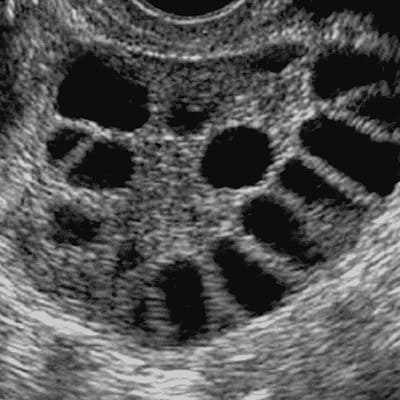

Síndrome de Ovario Poliquísticos